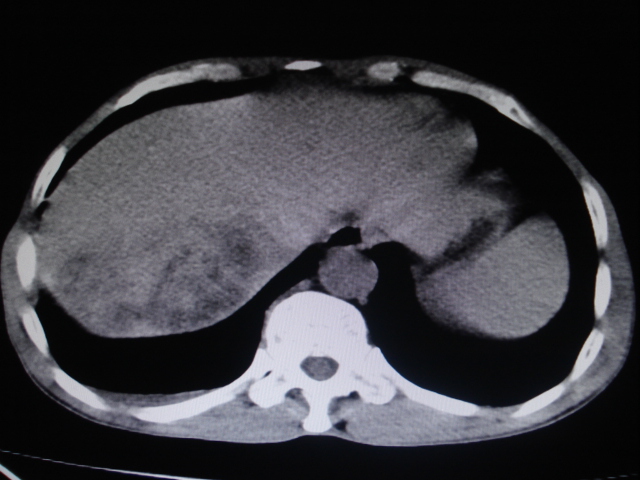

男性,62岁。肝右叶占位,平扫及增强如下,延迟期为15分钟扫描。